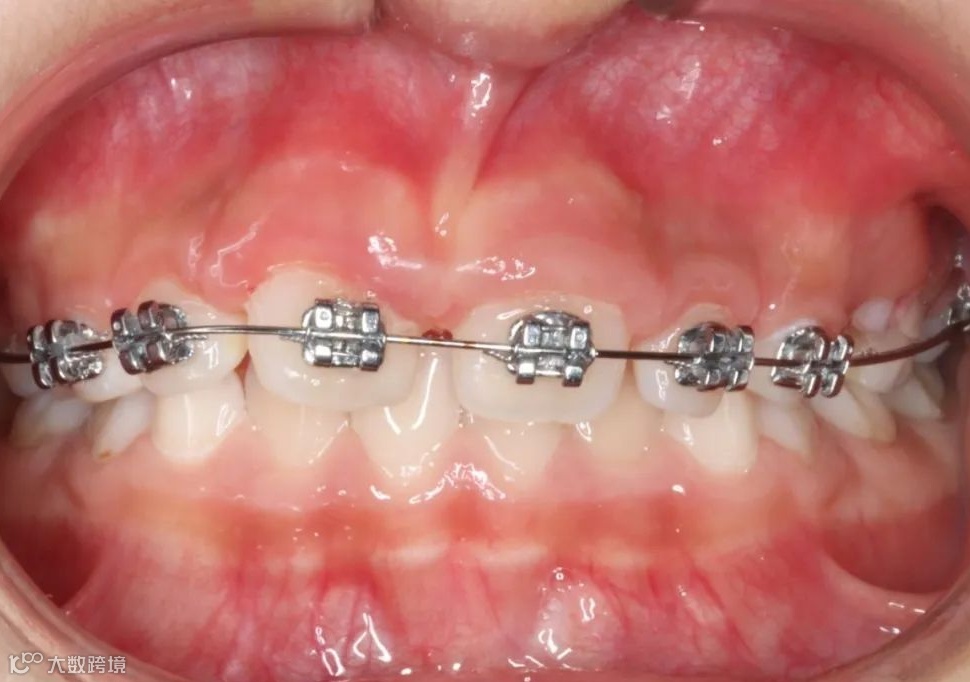

治疗前

治疗中(4个月后)

治疗后(6个月后)